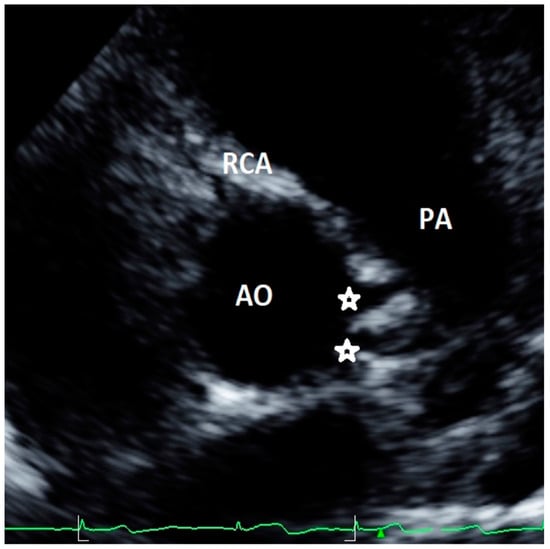

Figure 2. Asymptomatic 13-year-old boy evaluated with negative stress testing for murmur at preparticipation evaluation for sports competition. Parasternal short-axis view at the level of aortic root showing separate origins of circumflex (CFx) and left descending artery (LAD).

Minor AAOCAs were described for 1.5% [13] to 2.6% [19] of the cases: they included separate ostia for left anterior descending artery and CFx from left sinus, two distinct ostia in the right sinus for RCA and the conus branch, and a short left main coronary artery—<5 mm—or small fistulas. A case of minor AAOCA from our case series, with two distinct ostia originating from the left sinus, is shown in Figure 2. However, definition and clinical significance of minor and major AAOCAs varied among the studies. Indeed, the study by Lytrivi and colleagues [23], reporting the highest number of AAOCAs (111 patients out of a cohort of 14,546 subjects), did not distinguish between major and minor defects. Gerling et al. included into low-risk AAOCAs also high take-off of coronary arteries with acute angle that may be at risk of SCD [33]. Four studies did not evaluate minor AAOCAs [15,22,24,31].